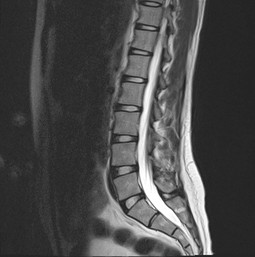

Degenerative Veranderungen Morbus Baastrup

Morbus Baastrup Wikipedia